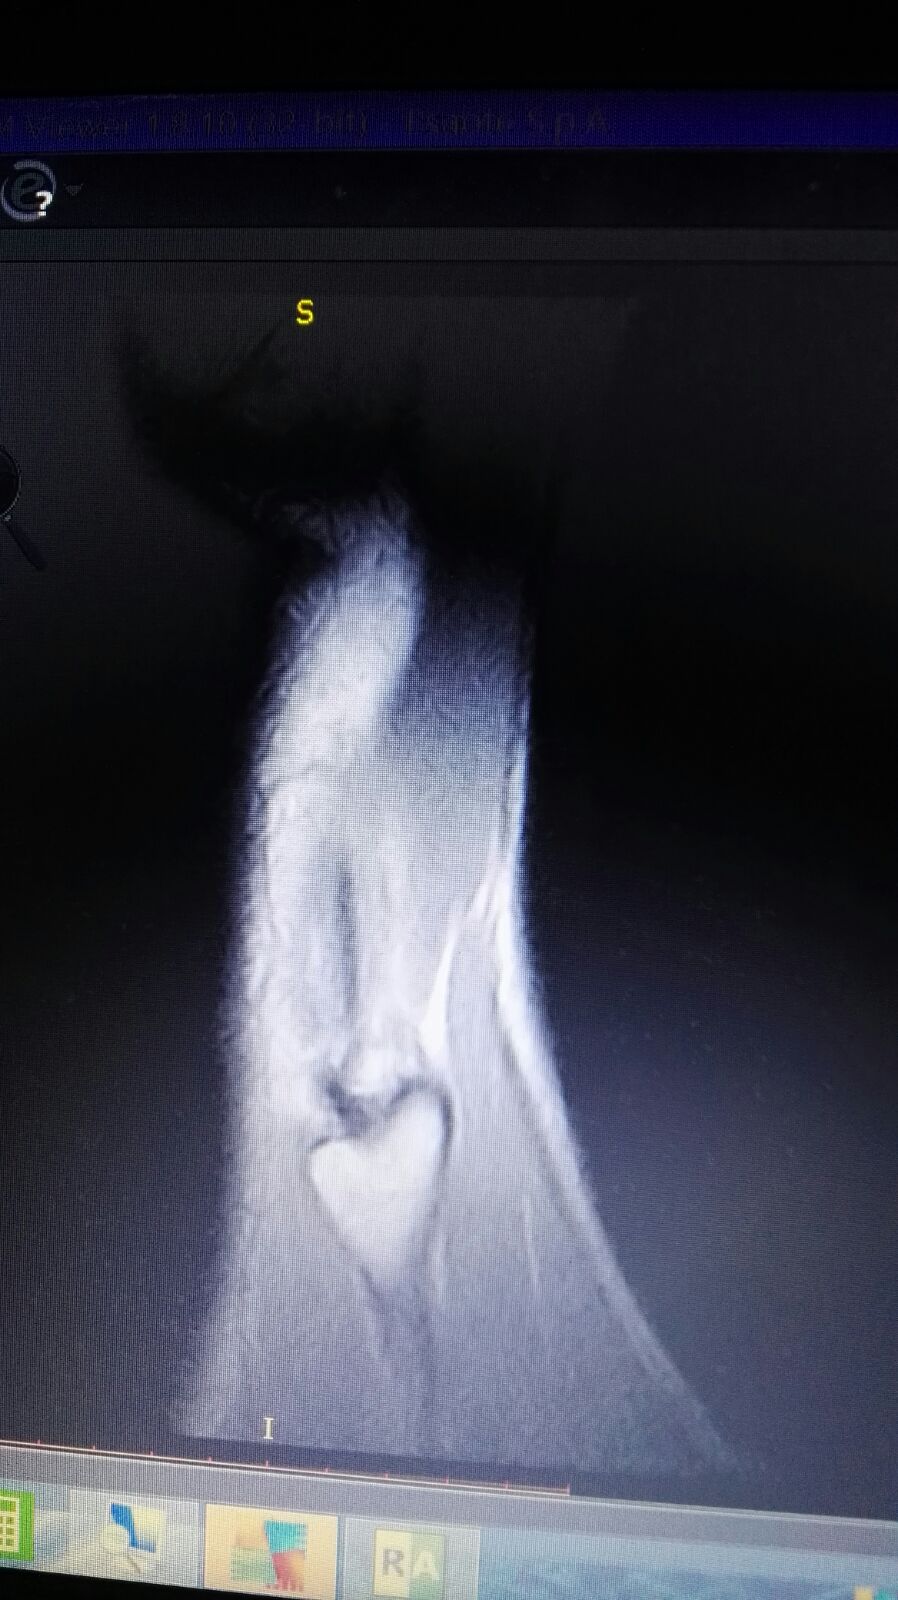

Le ho inviato qualche altra foto

IMG-20180301-WA0017.jpg

[ 239.83 KiB | Osservato 1320 volte ]